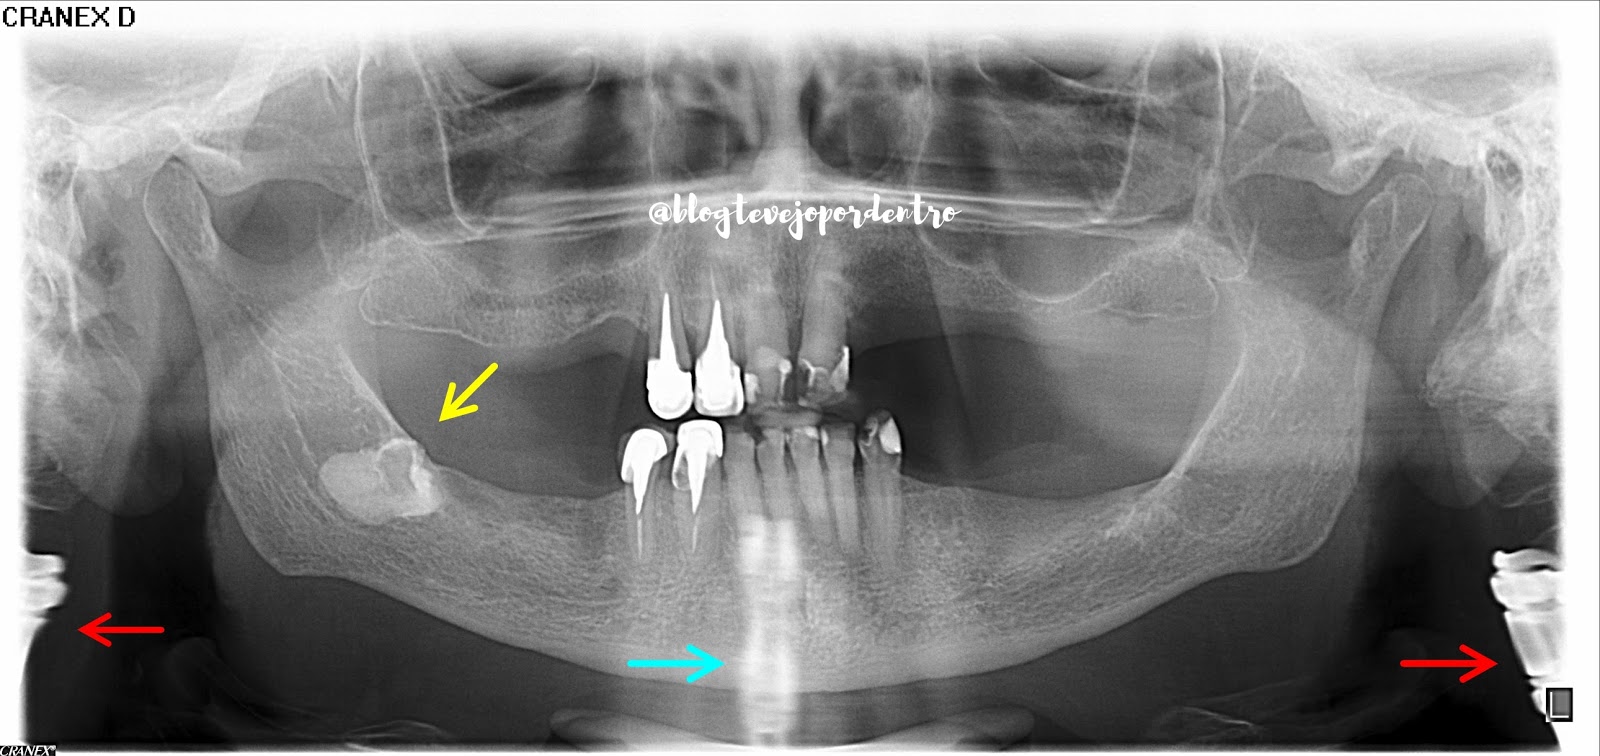

Neste Imagem Radiográfica da Semana, destacamos:

1. Seta amarela : dente incluso.

2. Setas vermelhas : imagem de parafusos na coluna cervical, compatível com artrodese.

3. Seta azul : "imagem fantasma" produzida pelos parafusos na região cervical.